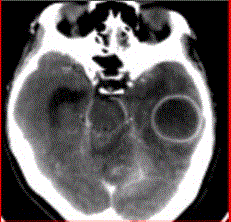

问题 患者女,26岁,头痛、低热10d余,既往有左侧慢性中耳炎病史。CT表现如下图。 脑脓肿的感染途径不包括

选项 A.中耳炎经鼓室盖直接蔓延 B.乳突炎直接蔓延 C.血栓性静脉炎所致 D.血行感染 E.淋巴途径感染

答案 E